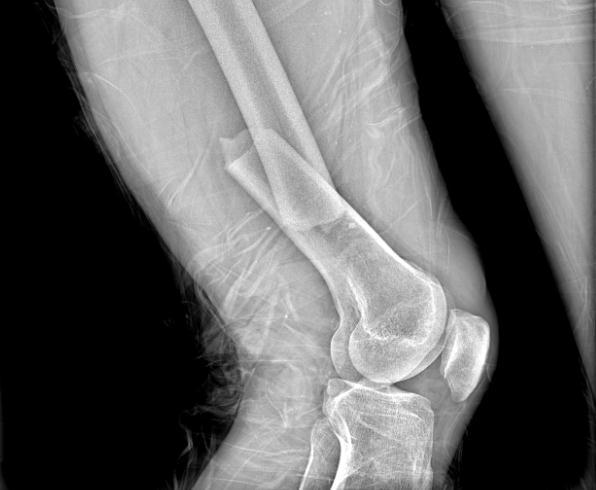

近日,57歲的秦先生因外傷傷及胸部、右大腿,劇烈疼痛,不能站立行走,呼叫120送至濟南南郊醫(yī)院急診中心救治。經診斷,秦先生為右股骨干骨折、肋骨骨折。

結合術前檢查及綜合評估,創(chuàng)傷組組長姜潼宇、主治醫(yī)生薛澤剛及團隊,針對右股骨干骨折采用右側股骨干骨折切開復位內固定術的微創(chuàng)手術。在右側股骨骨折端取8cm手術切口,放置長達15cm鋼板,骨折端切開插入鋼板,避免的開大刀,微創(chuàng)小切口,減少損傷。通過該微創(chuàng)手術,大大縮短了骨折愈合期,提高了患者的生活質量。目前,秦先生的右下肢已經能夠進行功能康復訓練。